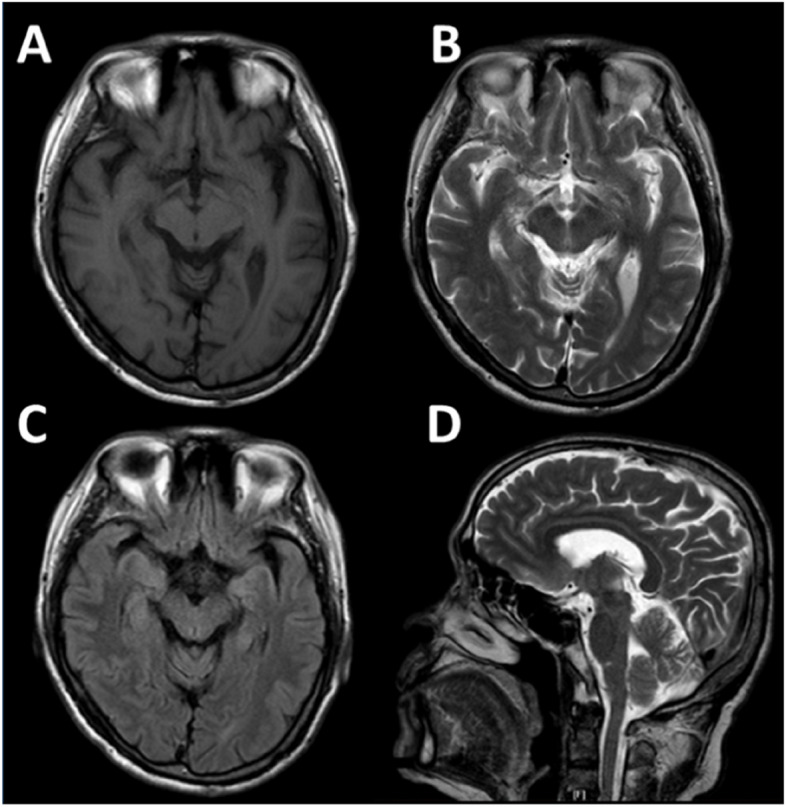

The male patient, who had always lived in Foshan city with an elevation of approximately 13 m in China, had never gone to the plateau region and had not previously complained of any neurologic symptoms. In 2013, he was 69, traveled to the Tibetan Plateau which has an elevation of approximately 4,000 m, and stayed for 3 days without a high-altitude reaction. When climbing Mt. Namjagbarwa Hill with an elevation of approximately 6,700 m, he suffered a headache, vomiting, and dizziness after a strong cold wind. He experienced paroxysmal vertigo, headache, malaise, and nausea, accompanied by bradykinesia and rigidity in the neck, which was diagnosed as an acute hypoxia reaction by a local doctor. These symptoms were partly relieved after oxygen inhalation therapy. One month after he returned to a low altitude of approximately 13 m, vertigo disappeared, but the acute bradykinesia and rigidity symptoms continued. He went to the hospital and was found to have a mask-like face and bilateral mild cogwheel rigidity but no action or resting tremor, and he denied any cognitive or psychiatric symptoms. He was diagnosed with PD for the first time and his UPDRS-III total score was 37. The laboratory tests and anal sphincter electromyogram were normal. Brain magnetic resonance imaging (MRI, Fig. 1) and magnetic resonance angiography (MRA) scans revealed mild multiple stenosis in the bilateral posterior cerebral arteries (PCAs). The patient started drug treatment with levodopa and pramipexole, and his bradykinesia and rigidity symptoms were significantly improved with the UPDRS motor score increasing by 65%.

Fig. 1.

Brain structure of PD patients with magnetic resonance imaging. The MRI imaging performed transverse scans of T1-weighted (A), T2-weighted (B), T2-weighted (C), and sagittal scans of T2-weighted (D) images in 2017. No severe morphological changes in the brain were reported